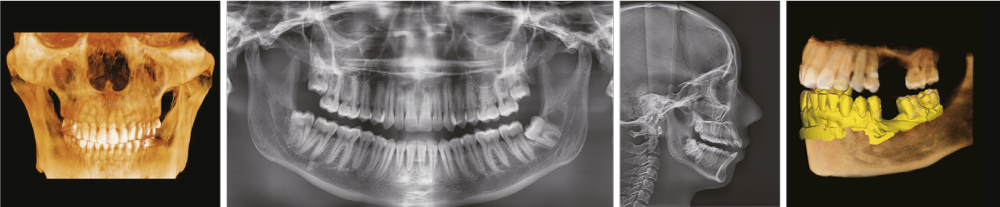

Новейшая цифровая рентгеновская система визуализации 4-в-1

INSIGHT 2.0

Функция Insight Pan служит для получения многослойных панорамных изображений, гарантирующих возможность наблюдать необходимую анатомию на нужной глубине. Insight 2.0 имеет обновленную функцию свободного FOV, что позволит исследовать только интересующую область.